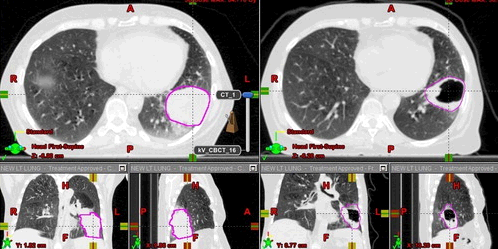

Image-guidance triggered adaptive replanning of radiation therapy for locally advanced lung cancer: an evaluation of cases requiring plan adaptation http://bit.ly/2QPKK9n

#radiology#chestrad#radoncpic.twitter.com/5intl8AyRm